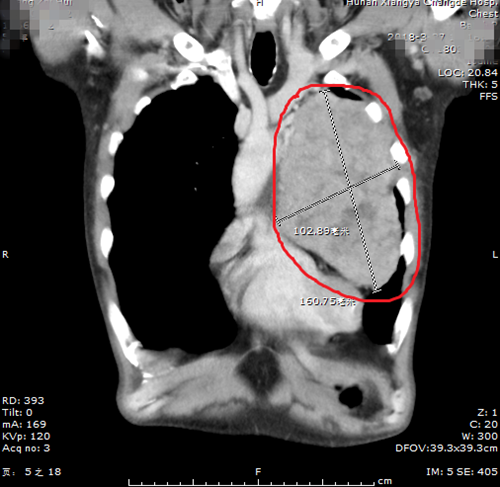

一次单位体检,意外发现左侧胸腔居然长了个 “坨”。黄大叔连忙来到湘雅常德医院心胸外科,进一步做了胸部增强CT检查。 经CT检查结果提示考虑为:显示左侧胸腔长了个“巨大肿瘤”,大小约17cm×11cm,已经压迫心脏、肺动脉、气管、肺等重要脏器,并且有典型的肿瘤压迫气管症状——反复阵发性干咳,平躺时症状加重。